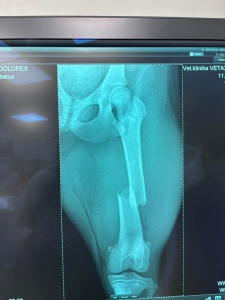

DOLORES má po operácii ♥. Ďakujeme všetkým za pomoc ♥♥♥. Držte malej palce aby bola čoskoro fit :)

Dolores po operácii pozdravuje. Zotavuje sa výborne a rýchlejšie ako sme mysleli ♥♥♥